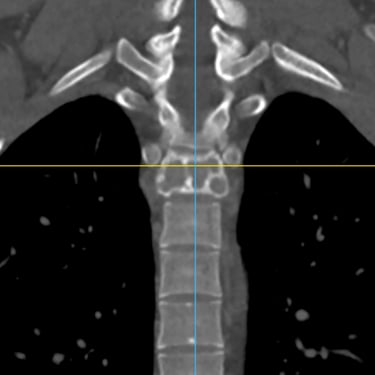

Tumor vertebral dorsal hemorrágico: descompresión medular, biopsia y artrodesis dorsal

El tumor vertebral dorsal puede ocasionar compresión de la médula espinal, dolor intenso y alteraciones neurológicas progresivas. En algunos casos, estos tumores presentan componente hemorrágico que incrementa la presión sobre las estructuras nerviosas. El tratamiento quirúrgico puede incluir descompresión medular para liberar la médula espinal, toma de biopsia para establecer el diagnóstico histopatológico y artrodesis dorsal con instrumentación para estabilizar la columna vertebral. Este abordaje permite reducir el riesgo de daño neurológico, aliviar los síntomas y mantener la estabilidad vertebral. La cirugía se realiza con técnicas especializadas que buscan preservar la función neurológica y mejorar la calidad de vida del paciente.